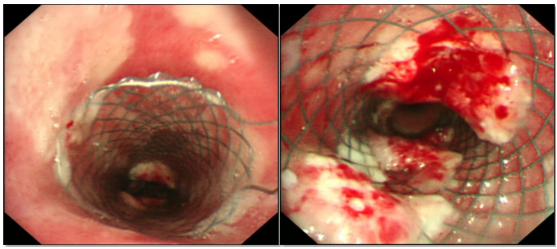

患者男性,65岁,肺鳞癌,气管中段外压性狭窄,气管金属支架置入术后13天,胸闷气急进行性加重,端坐位,指脉血氧饱和度80%~85%。

图片

支架植入术后7天,肿瘤已长入支架腔,清理后缓解。